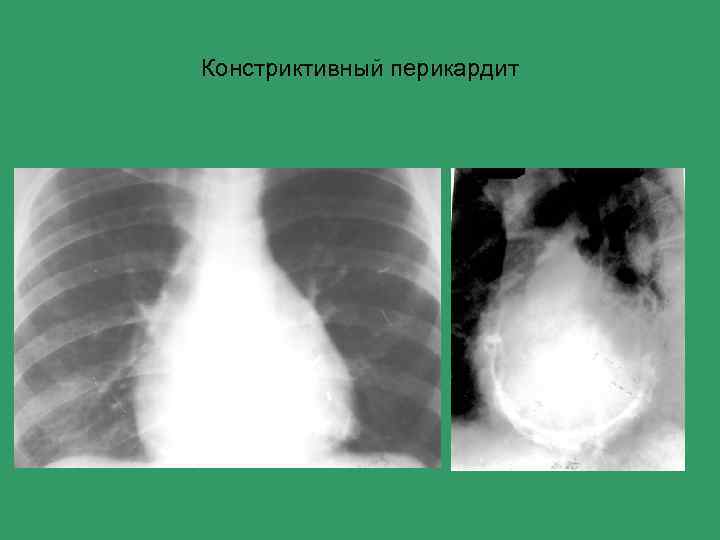

Констриктивный перикардит